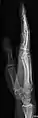

- Tibia and Fibula - AP and Lateral

- Ankle - AP/Mortice and Lateral